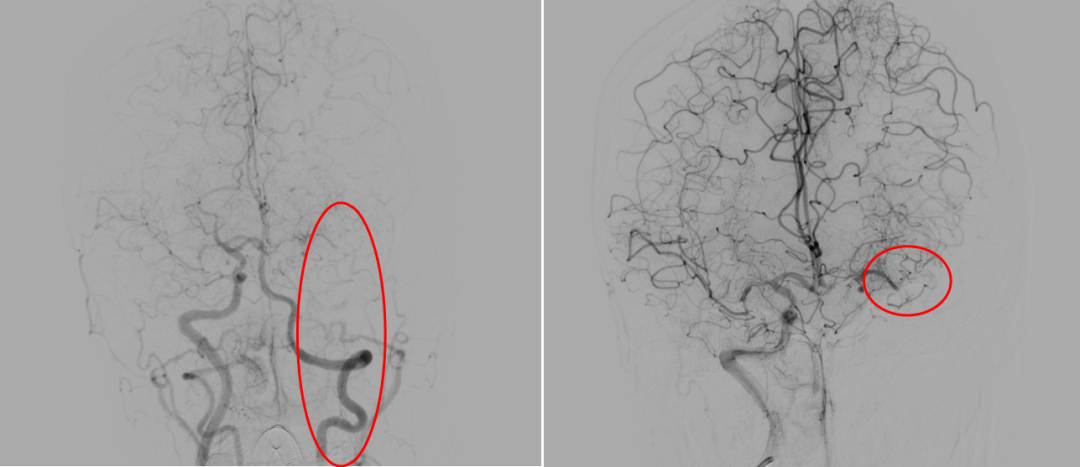

神经介入诊疗中心主任、副主任医师刘俊中接诊后,根据各项检查检验结果迅速判断张女士属于颅内大血管病变。

左侧大脑中动脉和颈内动脉均已闭塞,相当于左侧大脑半球几乎断了供血,手术指征明确。

5 分钟后,张女士被推进介入手术室,急诊脑血管造影进一步确认了血管闭塞情况。

10 分钟后,手术顺利完成,堵塞血管成功开通,濒临坏死的脑细胞被及时 “救回”,张女士的病情得到了有效控制。